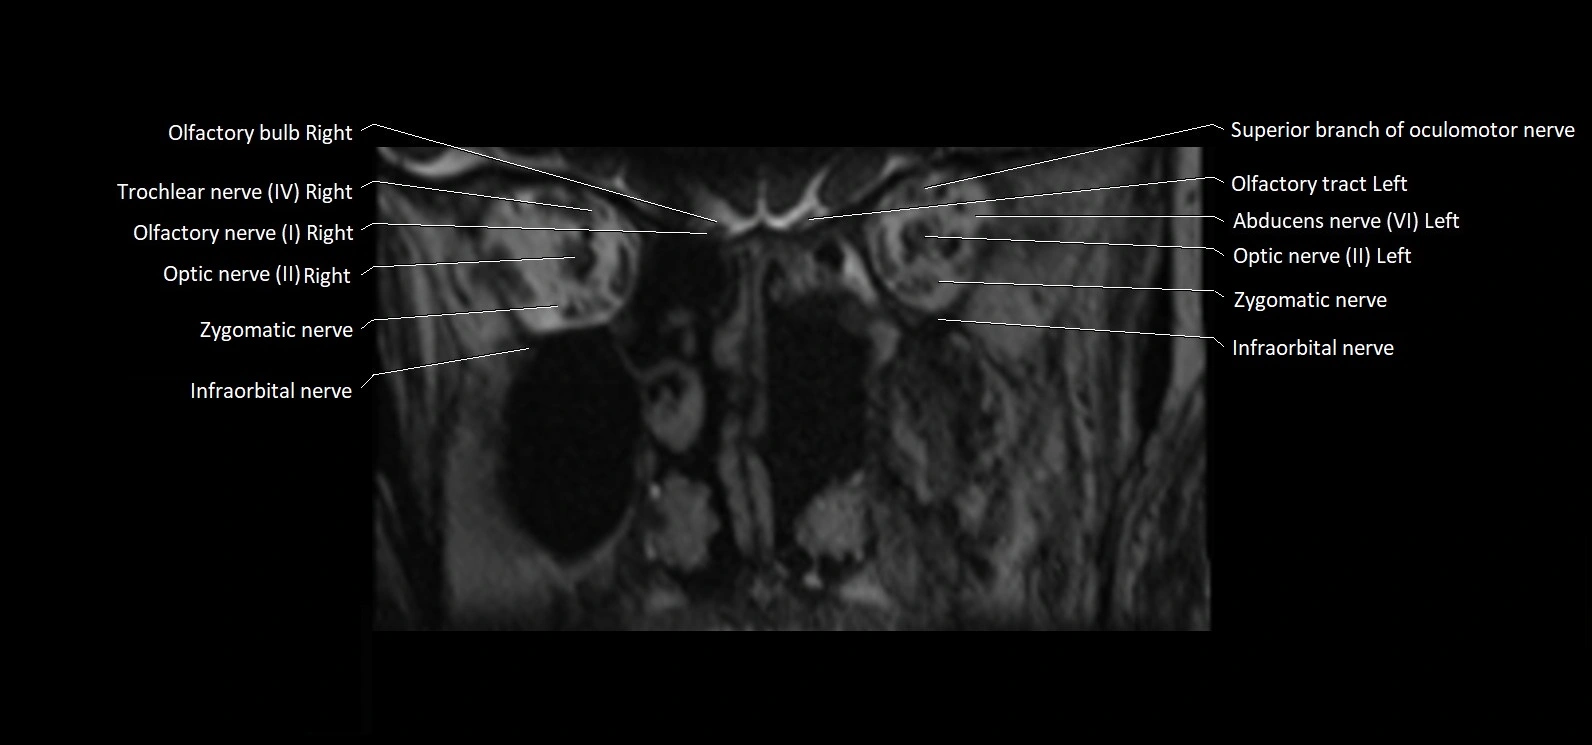

MRI Appearance

• The abducens nerve is a small, thin, linear structure

• Best visualized on high-resolution T2-weighted 3D MRI sequences (e.g., FIESTA or CISS)

• Seen as a hypointense (dark) line running from the brainstem at the pontomedullary junction, traversing the prepontine cistern, and entering Dorello’s canal under the petrosphenoidal ligament, then into the cavernous sinus, and finally the orbit

• May be challenging to visualize in standard MRI due to its small size

• Pathology may be inferred by absence, displacement, or enhancement of the nerve

MRI images

image